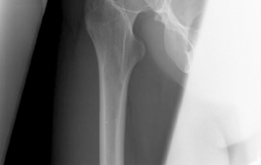

The radiographic evaluation of the dysplastic hip requires a highly standardized and rigorous protocol to accurately quantify the three-dimensional deformity. The initial assessment begins with a standing anteroposterior (AP) radiograph of the pelvis. In this patient, the AP view immediately reveals the hallmark signs of DDH: decreased anterolateral coverage of the femoral head and a broken Shenton line. The broken Shenton line—a step-off between the medial border of the femoral neck and the inferior border of the superior pubic ramus—indicates proximal and lateral migration of the femoral head due to structural instability. Furthermore, we observe an increased Tönnis angle (acetabular inclination) and a significantly reduced Lateral Center Edge Angle (LCEA) of Wiberg, confirming the diagnosis of severe lateral uncoverage.

Beyond the AP pelvis, the False Profile view of Lequesne and de Sèze is mandatory to evaluate anterior coverage, which is frequently deficient in DDH. This view allows for the measurement of the Anterior Center Edge Angle (ACEA). In this patient, the ACEA is markedly reduced, correlating directly with her positive anterior apprehension test and the anterior location of her labral tear. We must also scrutinize the AP radiograph for signs of acetabular retroversion, such as the crossover sign, ischial spine sign, and posterior wall sign. Dysplasia is rarely a simple lack of lateral coverage; it is often a complex, multi-planar deformity where the acetabulum is not only shallow but also maloriented in the sagittal and axial planes.